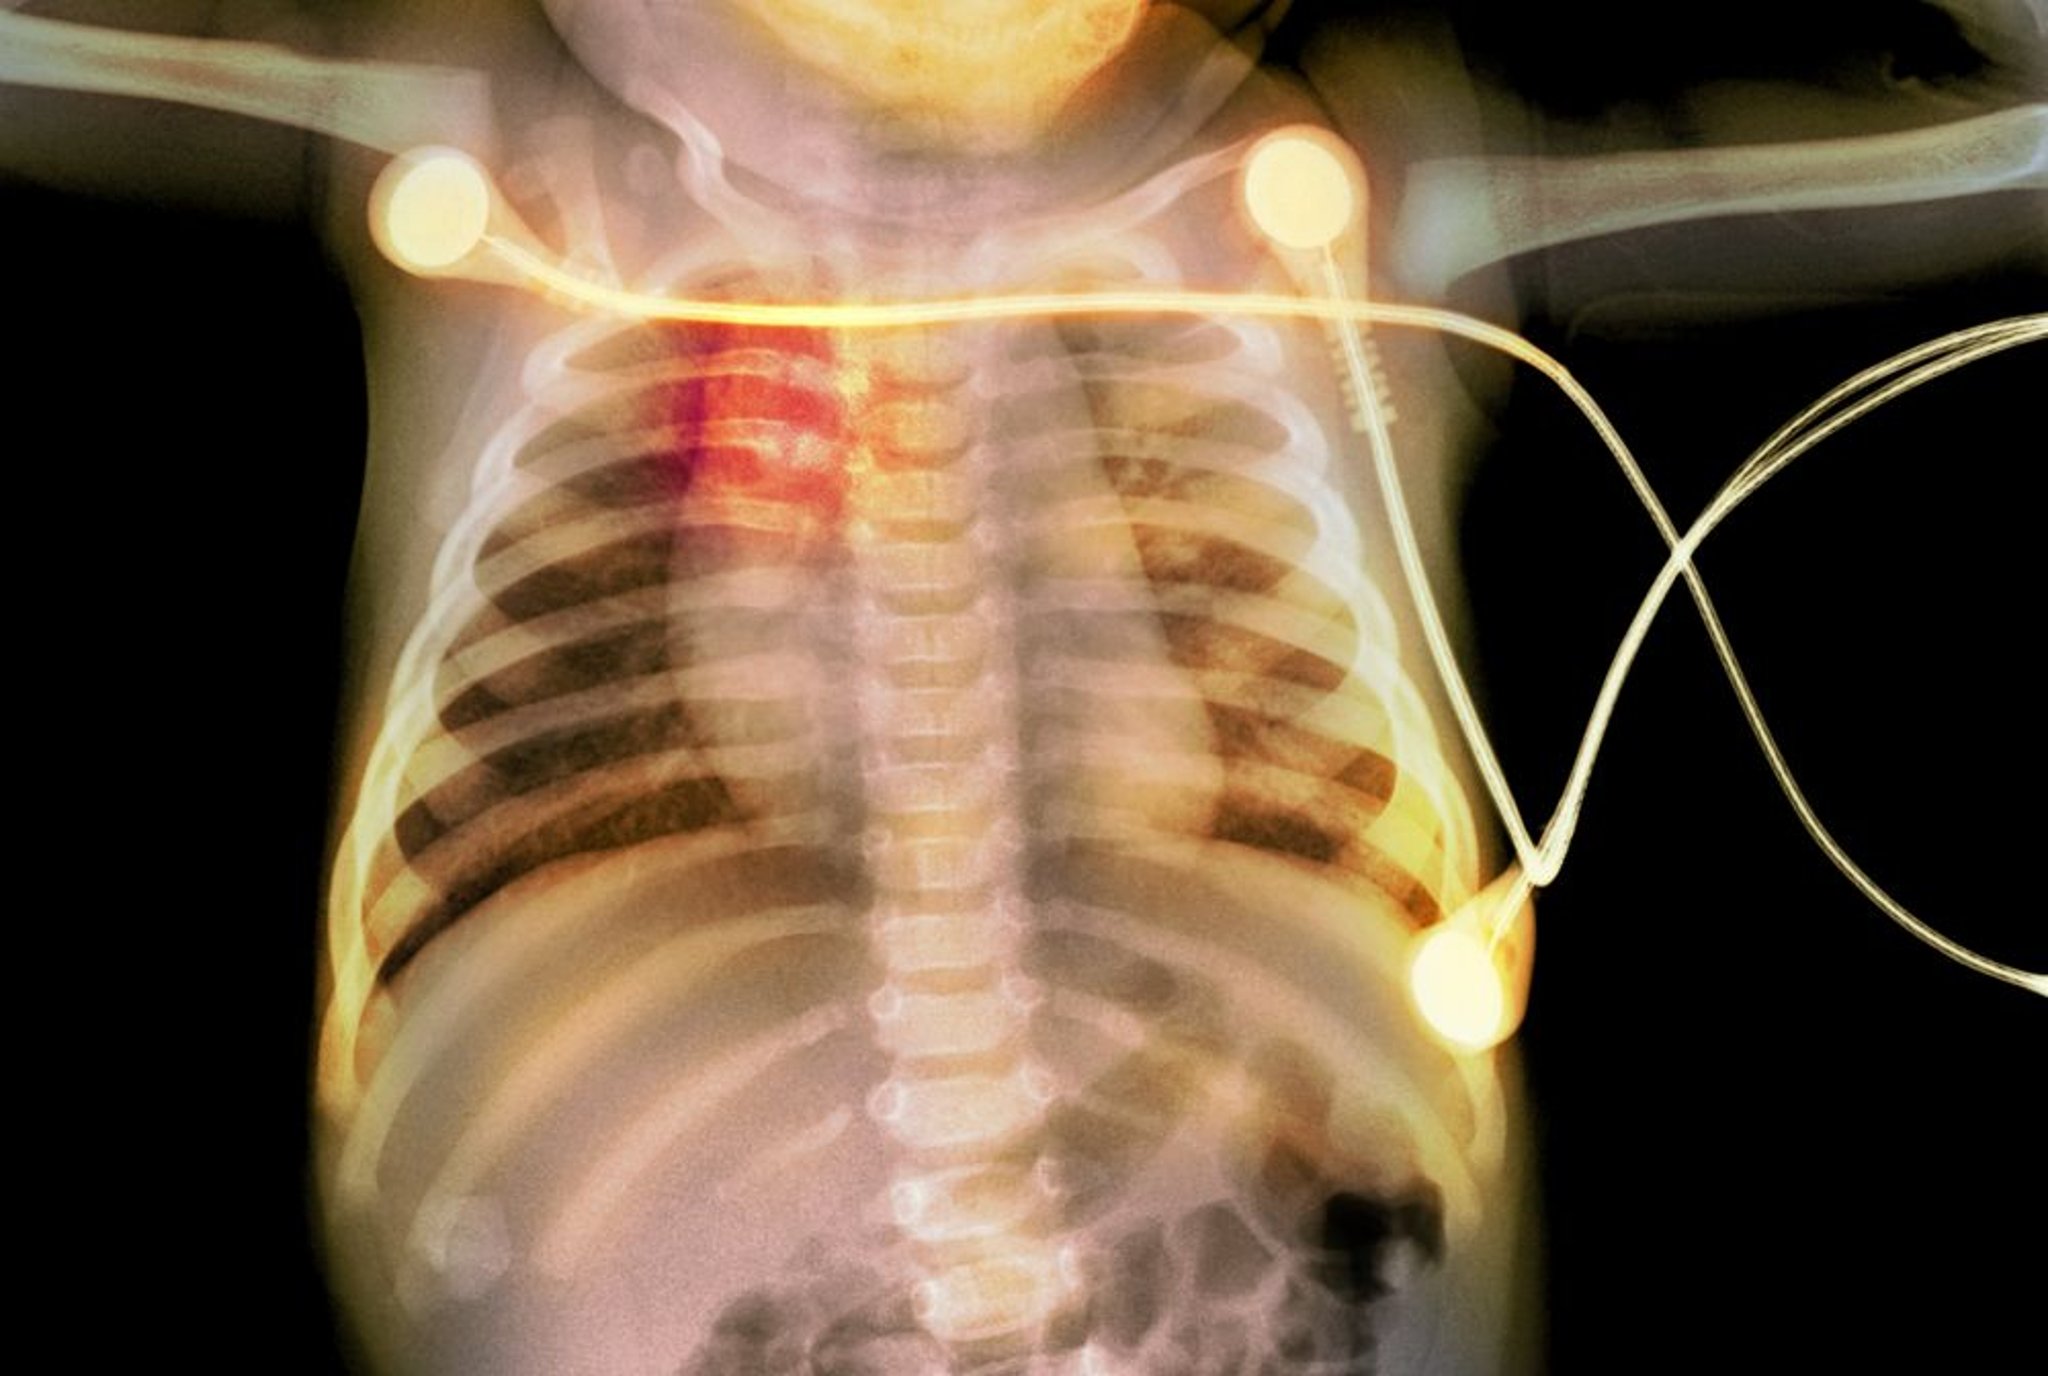

बच्चे की पसलियों में फ्रैक्चर

इस एक्स-रे में एक बच्चे में पसलियों में फ्रैक्चर (लाल रंग में हाइलाइट) दिख रहा है, जो बाल शोषण का संकेत है।